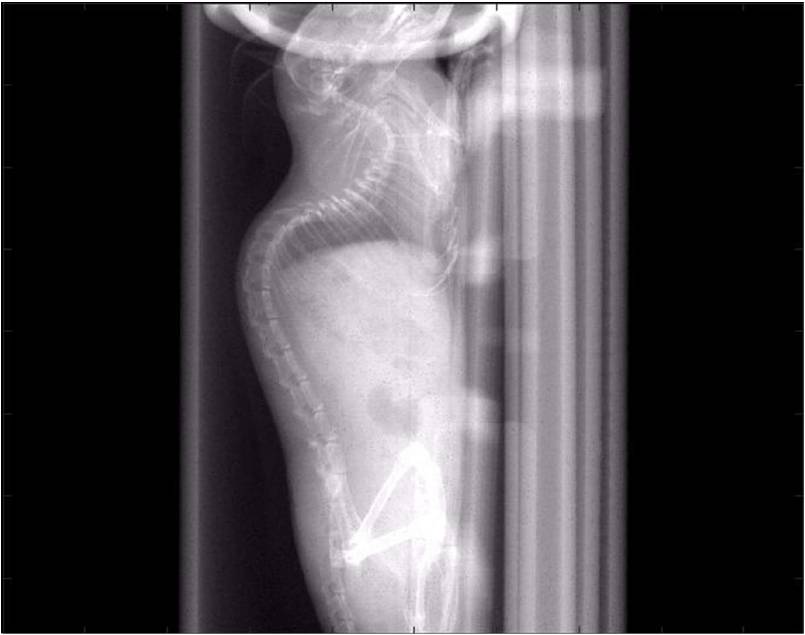

小鼠X光.jpg

• 掃描時間:2秒(高速模式)

• 2μm高分辨率影像